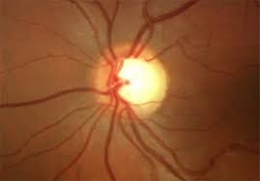

Con motivo de la Semana del Glaucoma, nuestra Cátedra junto se une en la Campaña Mundial para control, educación y detección de pacientes con glaucoma.

Recordemos que según el estudio RAAB, el glaucoma es la primera causa de ceguera irreversible en el Uruguay.